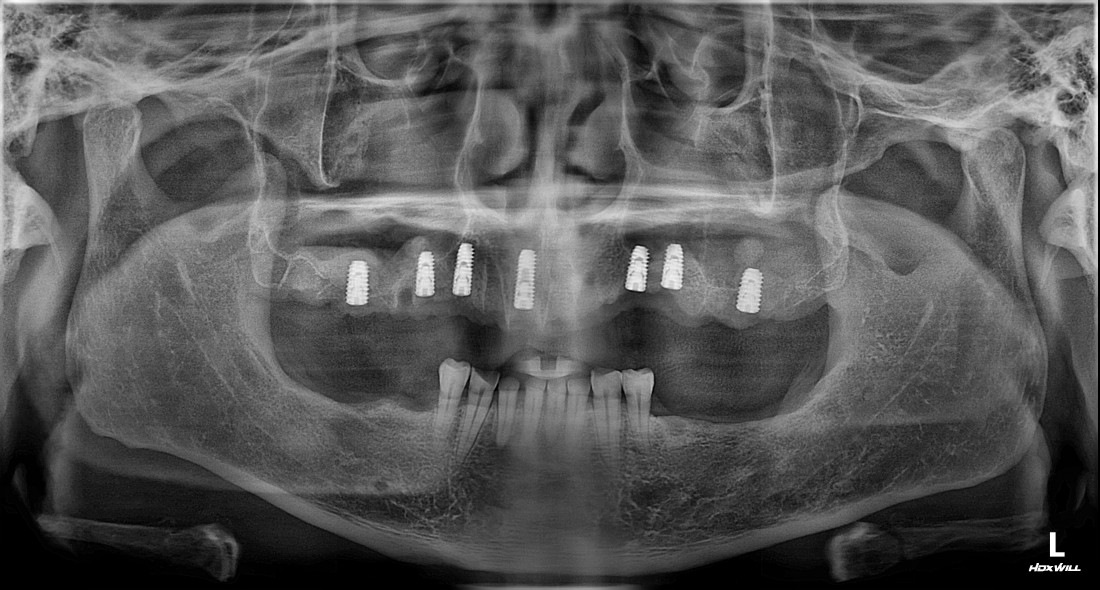

수완동 임플란트 치과에서는

보험 임플란트를 비롯하여

다양한 임플란트 케이스를

다 진료할 수 있는

경험많은 구강외과 전문의 진료가 가능합니다.

디지털 가이드 임플란트를 이용하여

잇몸절개를 최소화하기 때문에

붓기, 출혈, 통증이 현저히 적으며

수술 시간 역시 짧습니다.